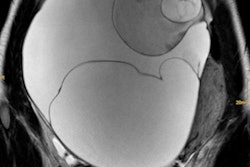

Using version 5.0 of the Slice-O-Matic software (Tomovision), the researchers extracted skeletal muscle area, skeletal muscle density, subcutaneous adipose tissue, and visceral adipose tissue data from an axial CT image at the level of the L3 vertebrae.